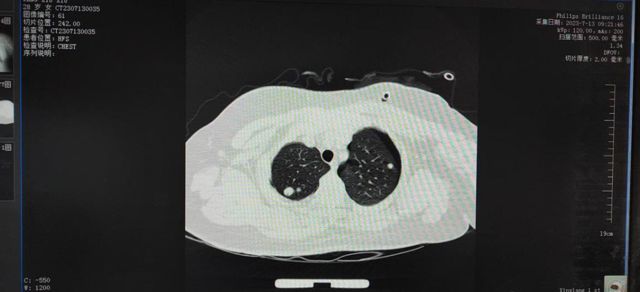

经胸部CT检查:左侧气胸,右侧少量液气胸,双肺多发结节。主管医生李宏伟了解到患者2年曾前在郑州某医院就诊并行手术治疗。此次检查发现双肺多发占位,诊断为双侧多发肿物,淋巴肌瘤并左侧气胸.关于淋巴管平滑肌瘤病(LAM),或许大家并不熟悉这个名词,但在医学界,它因其罕见性而备受关注。它就像一个谜一样神秘,只针对年轻女性,是一种病因未明,由于滑肌异常增殖导致支气管,淋巴管和小血管阻塞,呈进行性发展的全身性疾病。平均发生率约每100万女性人口中4.9人。肺部最易受累,常表现为弥漫性间质性肺疾病,因此称LAM为肺淋巴管平滑肌瘤症。